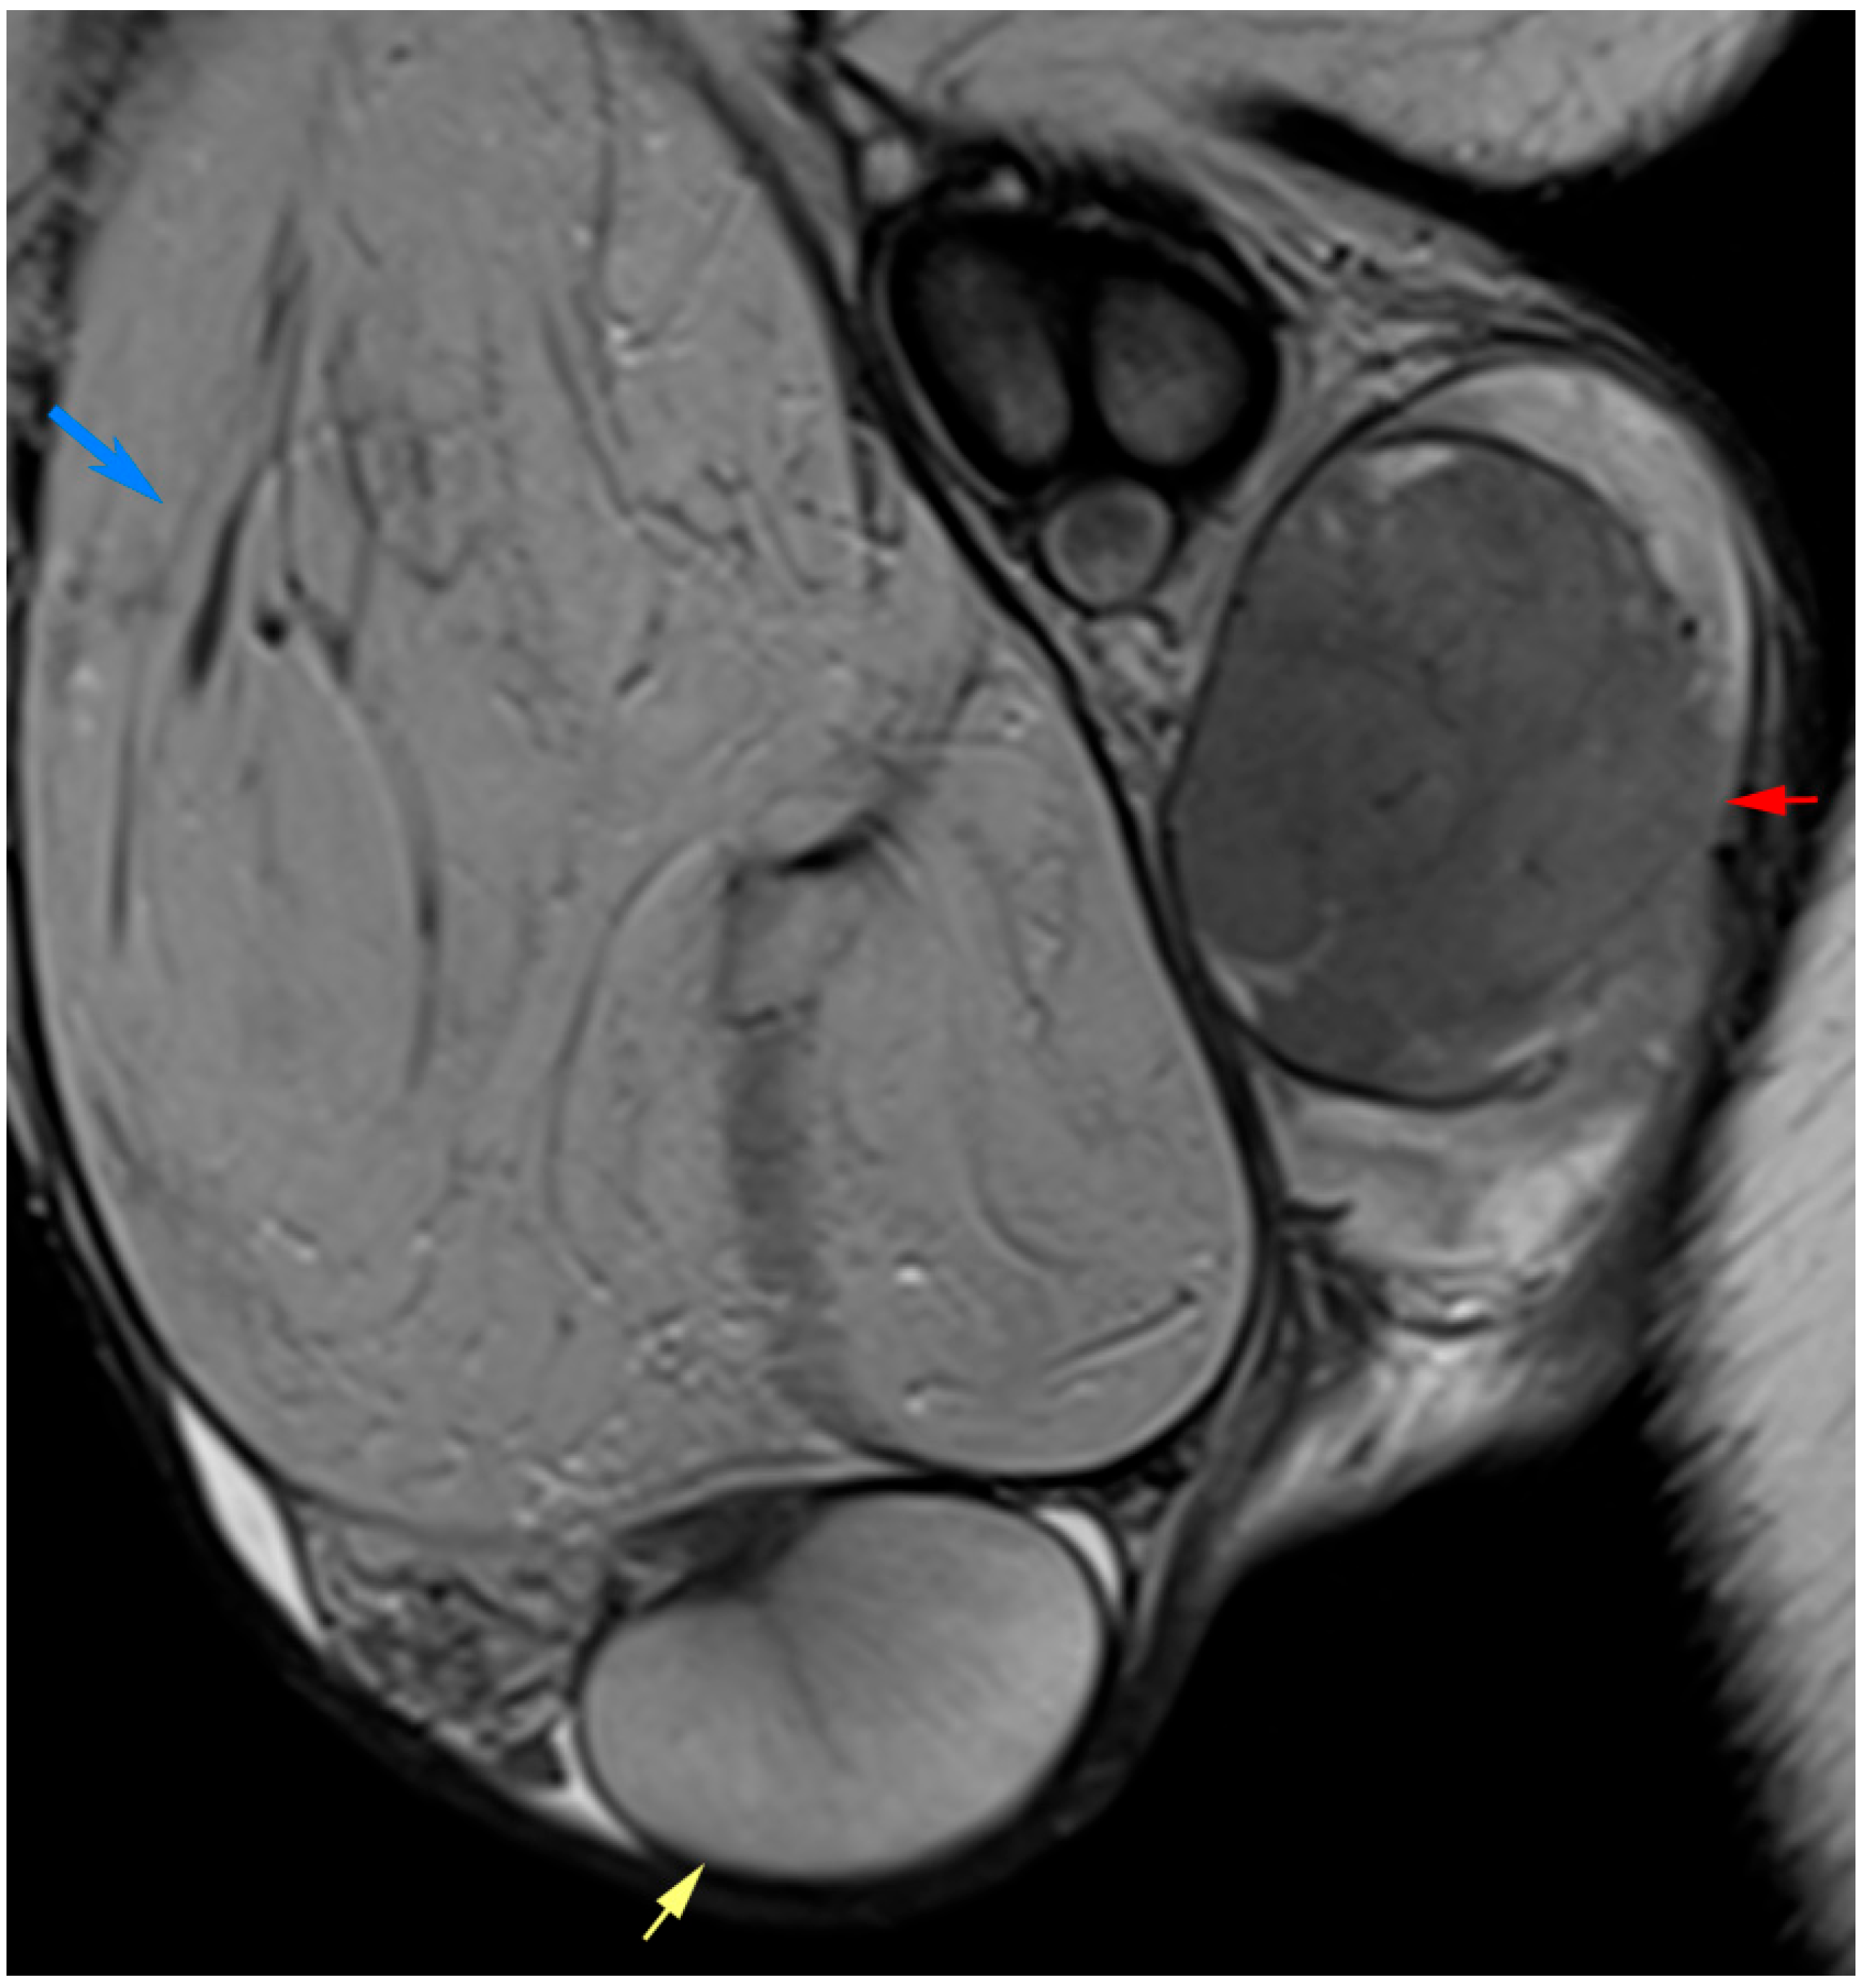

3.3.2. Paratesticular and Extratesticular Masses

3.4. Infertility